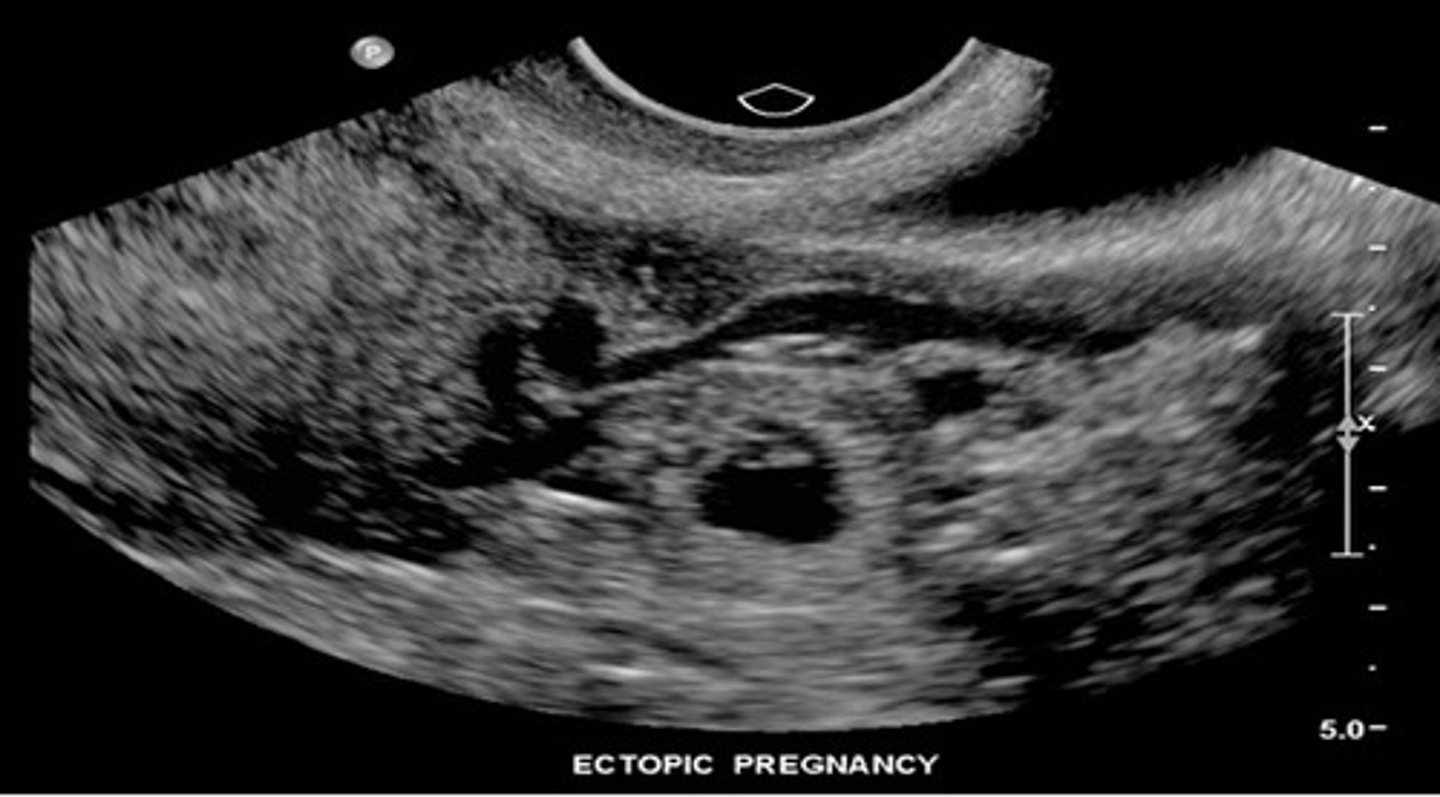

What are complications with assisted reproductive technology?

1. ovarian hyperstimulation

2. multiple gestations (25% chance)

3. ectopic pregnancy

If hCG is 1000 to 2000 mIU/mL and pregnancy is not seen within uterus, rule out ___

ectopic pregnancy